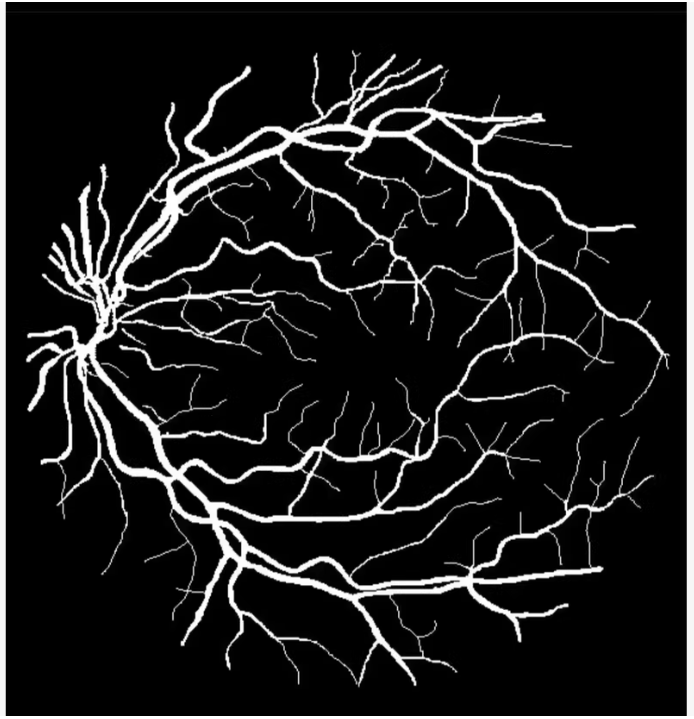

收集和标注眼底血管图像数据集,用于训练UNet模型进行图像分割。常用的公开数据集有DRIVE、STARE等。

数据预处理

对数据进行预处理,包括裁剪、缩放、归一化等操作,以便于模型训练。